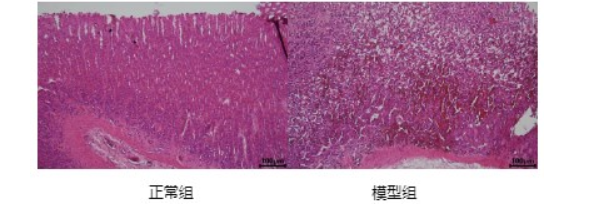

实验大鼠胃黏膜病理组织学改变(HE100×)

醋酸型胃溃疡大鼠胃组织HE 染色切片图

胃组织HE染色